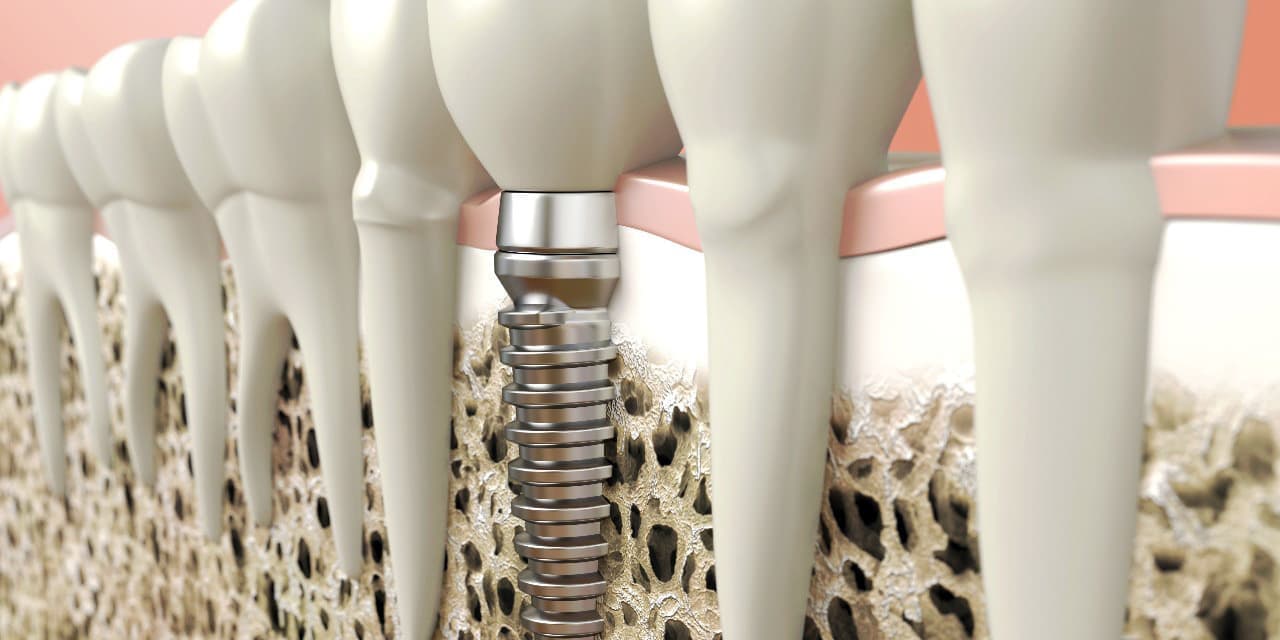

埋め込む金属に生体との親和性が高いチタンが使われる事が多く、チタンは長年の臨床研究でインプラントの素材として最も安全であり、また顎の骨としっかり結合することが確認されています。